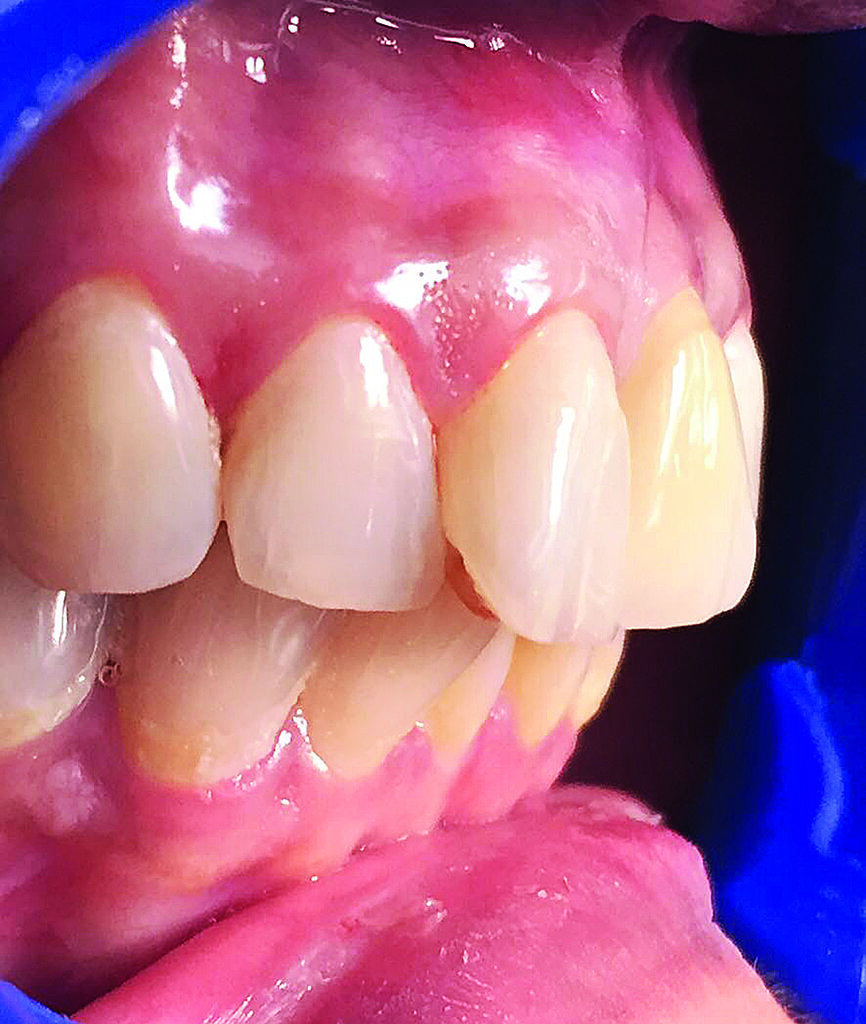

La patiente, âgée de 36 ans, nous a consulté pour un contrôle dentaire en raison d’une douleur dans la région des dents antérieures supérieures gauches. À ses dires, la douleur commençait subitement et s’aggravait lors de la mastication. L’examen clinique de l’incisive centrale supérieure gauche (dent 21) a révélé une inflammation, une douleur à la percussion et une fracture de la dent au niveau de la limite cervicale. La dent avait fait l’objet d’un traitement endodontique trois ans plus tôt et n’avait jamais été restaurée auparavant. Une radiographie a montré une couronne fracturée touchée par une résorption radiculaire mineure ainsi qu’une infection périapicale (Figs. 1a–c). L’examen radiographique comme l’examen clinique ont également confirmé la présence d’une largeur et d’une hauteur d’os suffisantes. Le pronostic très défavorable d’un retraitement endodontique a été expliqué à la patiente et elle a opté pour un traitement plus radical. La décision d’extraire la dent et de la remplacer immédiatement par un implant monobloc en zircone a donc été prise.

Fig. 1a : Photographie clinique préopératoire de la dent 21.